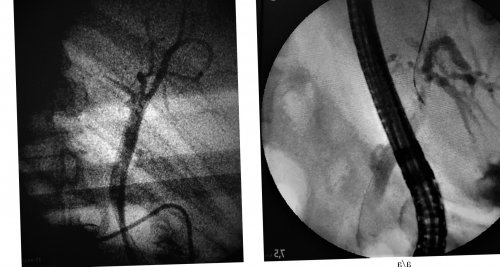

Рис. 2. Холангиограммы.

а — экстравазация контрастного вещества желтухи. В кн.: Коков Л.С., Черная Н.Р., Кулезнева Ю.В. (ред.) Лучевая диагностика и

(рис. 2, а)(рис. 2, б)